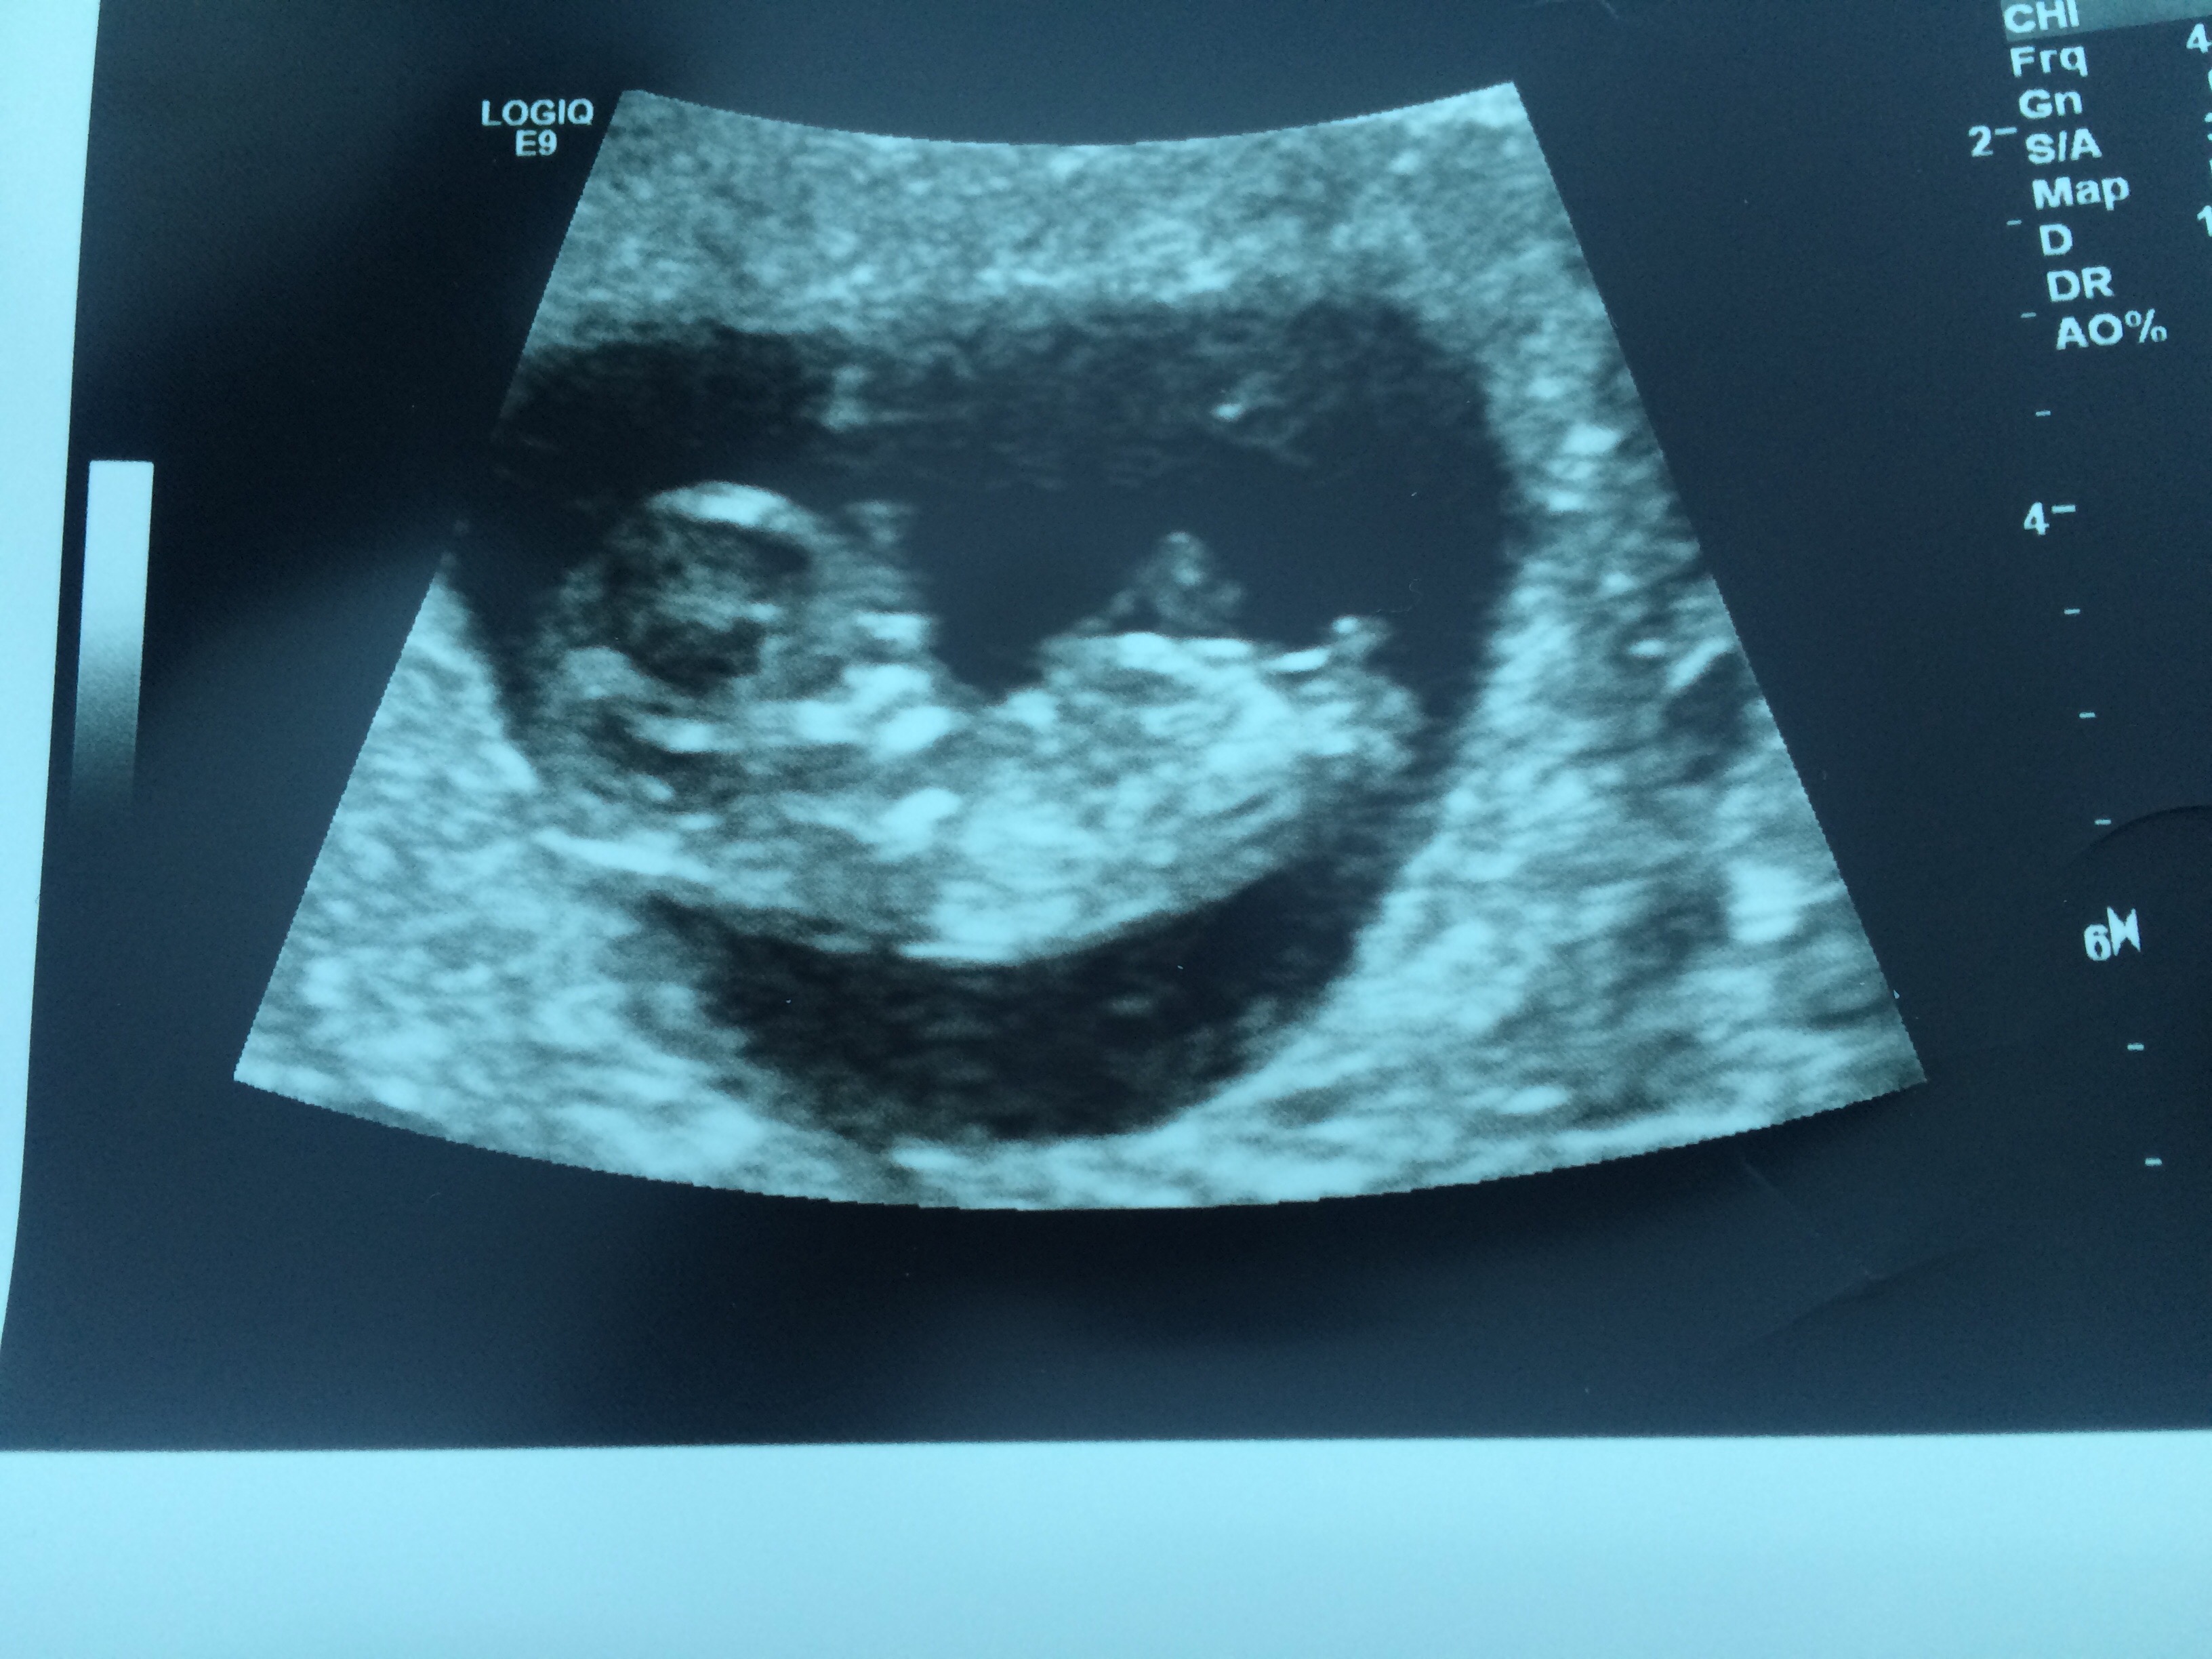

Please can you tell me if this is a boy or girl nub. Gestation was 11+5 but measured 11weeks Attachment 34024

depends on gestation and fair warning that baby does have its spine and butt curved just a bit. I had shots like this with 2 of my DD's and they were all girl. At 11+5 and 12 weeks respective they looked like that, and indeed very boyish look, but still ended up girls...so again, depends on gestation.

Not sure. What is the exact gestation? More pics?

Thank you for your replies. Gestation was 11+5 but measured 11 weeks..Attachment 34023

All boy for sure! Just seen gestation age..it looks boyish but at that gestation age it's not at all accurate!

Maybe boy, but too early